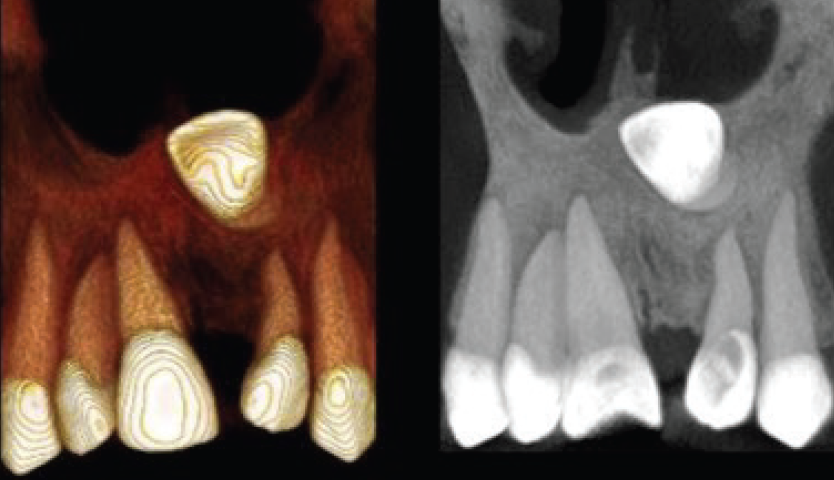

• Reabsorções dentárias

• Tipos: substituição, radicular interna, cervical externa, radicular externa